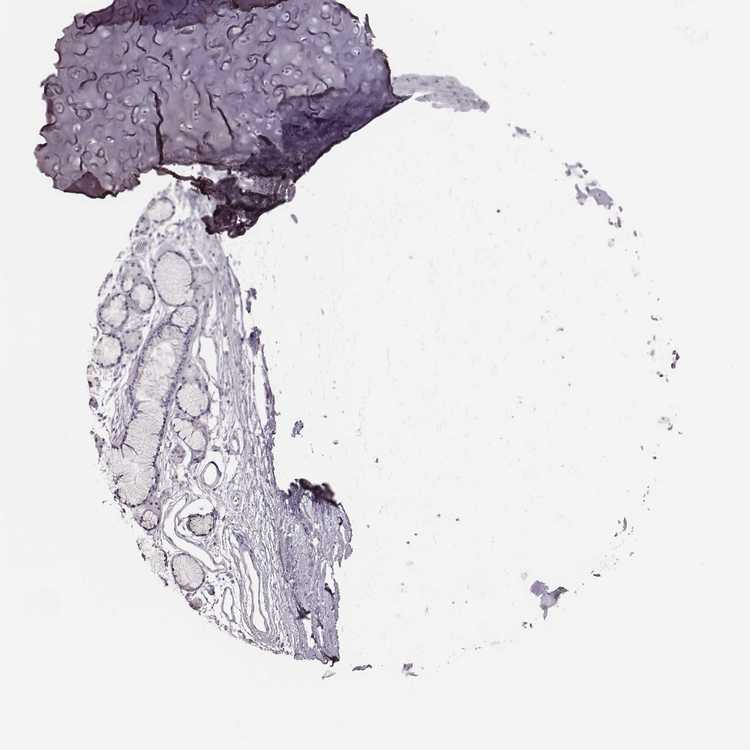

SOFT TISSUE 1 - Antibody stainingi

Antibody staining in the annotated cell types in the current human tissue is reported as not detected, low, medium, or high, based on conventional immunohistochemistry profiling in selected tissues. This score is based on the combination of the staining intensity and fraction of stained cells.

Each image is clickable and will lead to virtual microscopy that enables deeper exploration of all samples and also displays staining intensity scores, fraction scores and subcellular localization as well as patient and tissue information for each sample.

Antibody HPA007131

Chondrocytes Not detected

Fibroblasts Not detected

SOFT TISSUE 2 - Antibody stainingi

Peripheral nerve Not detected